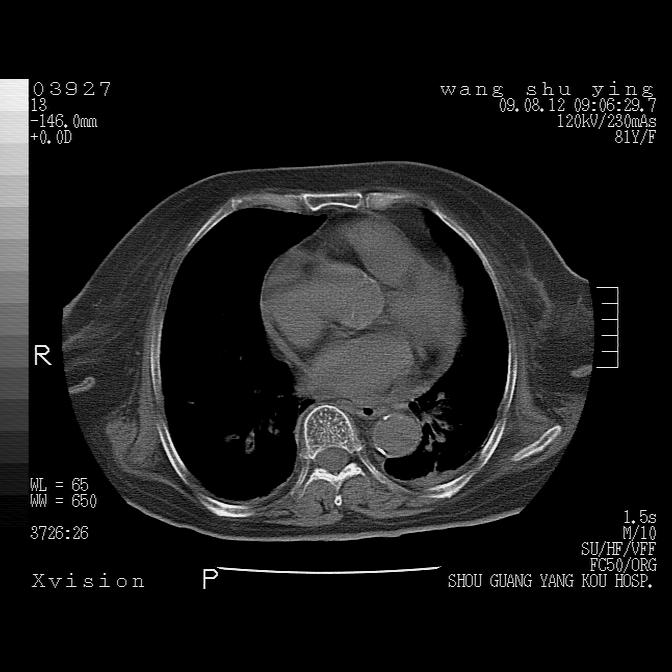

以下是引用帅河马在2009-8-12 12:59:00的发言:[br]两肺感染性病变伴双侧胸膜肥厚。[br]左侧甲状腺腺瘤不除外。[br]腹水+心包积液。[br][br][本贴已被 帅河马 于 2009-8-12 13:14:32 修改过]

以下是引用sdzyy在2009-8-12 18:17:00的发言:[br]两肺感染性病变伴双侧胸膜肥厚。[br]左侧甲状腺腺瘤不除外。[br]腹水+心包积液。[br]支持

以下是引用随光逐影在2009-8-12 19:42:00的发言:[br]1)两肺感染性病变伴双侧胸膜肥厚。2)不排除左侧甲状腺腺瘤。3)肝脏占位性病变;建议行进一步检查。